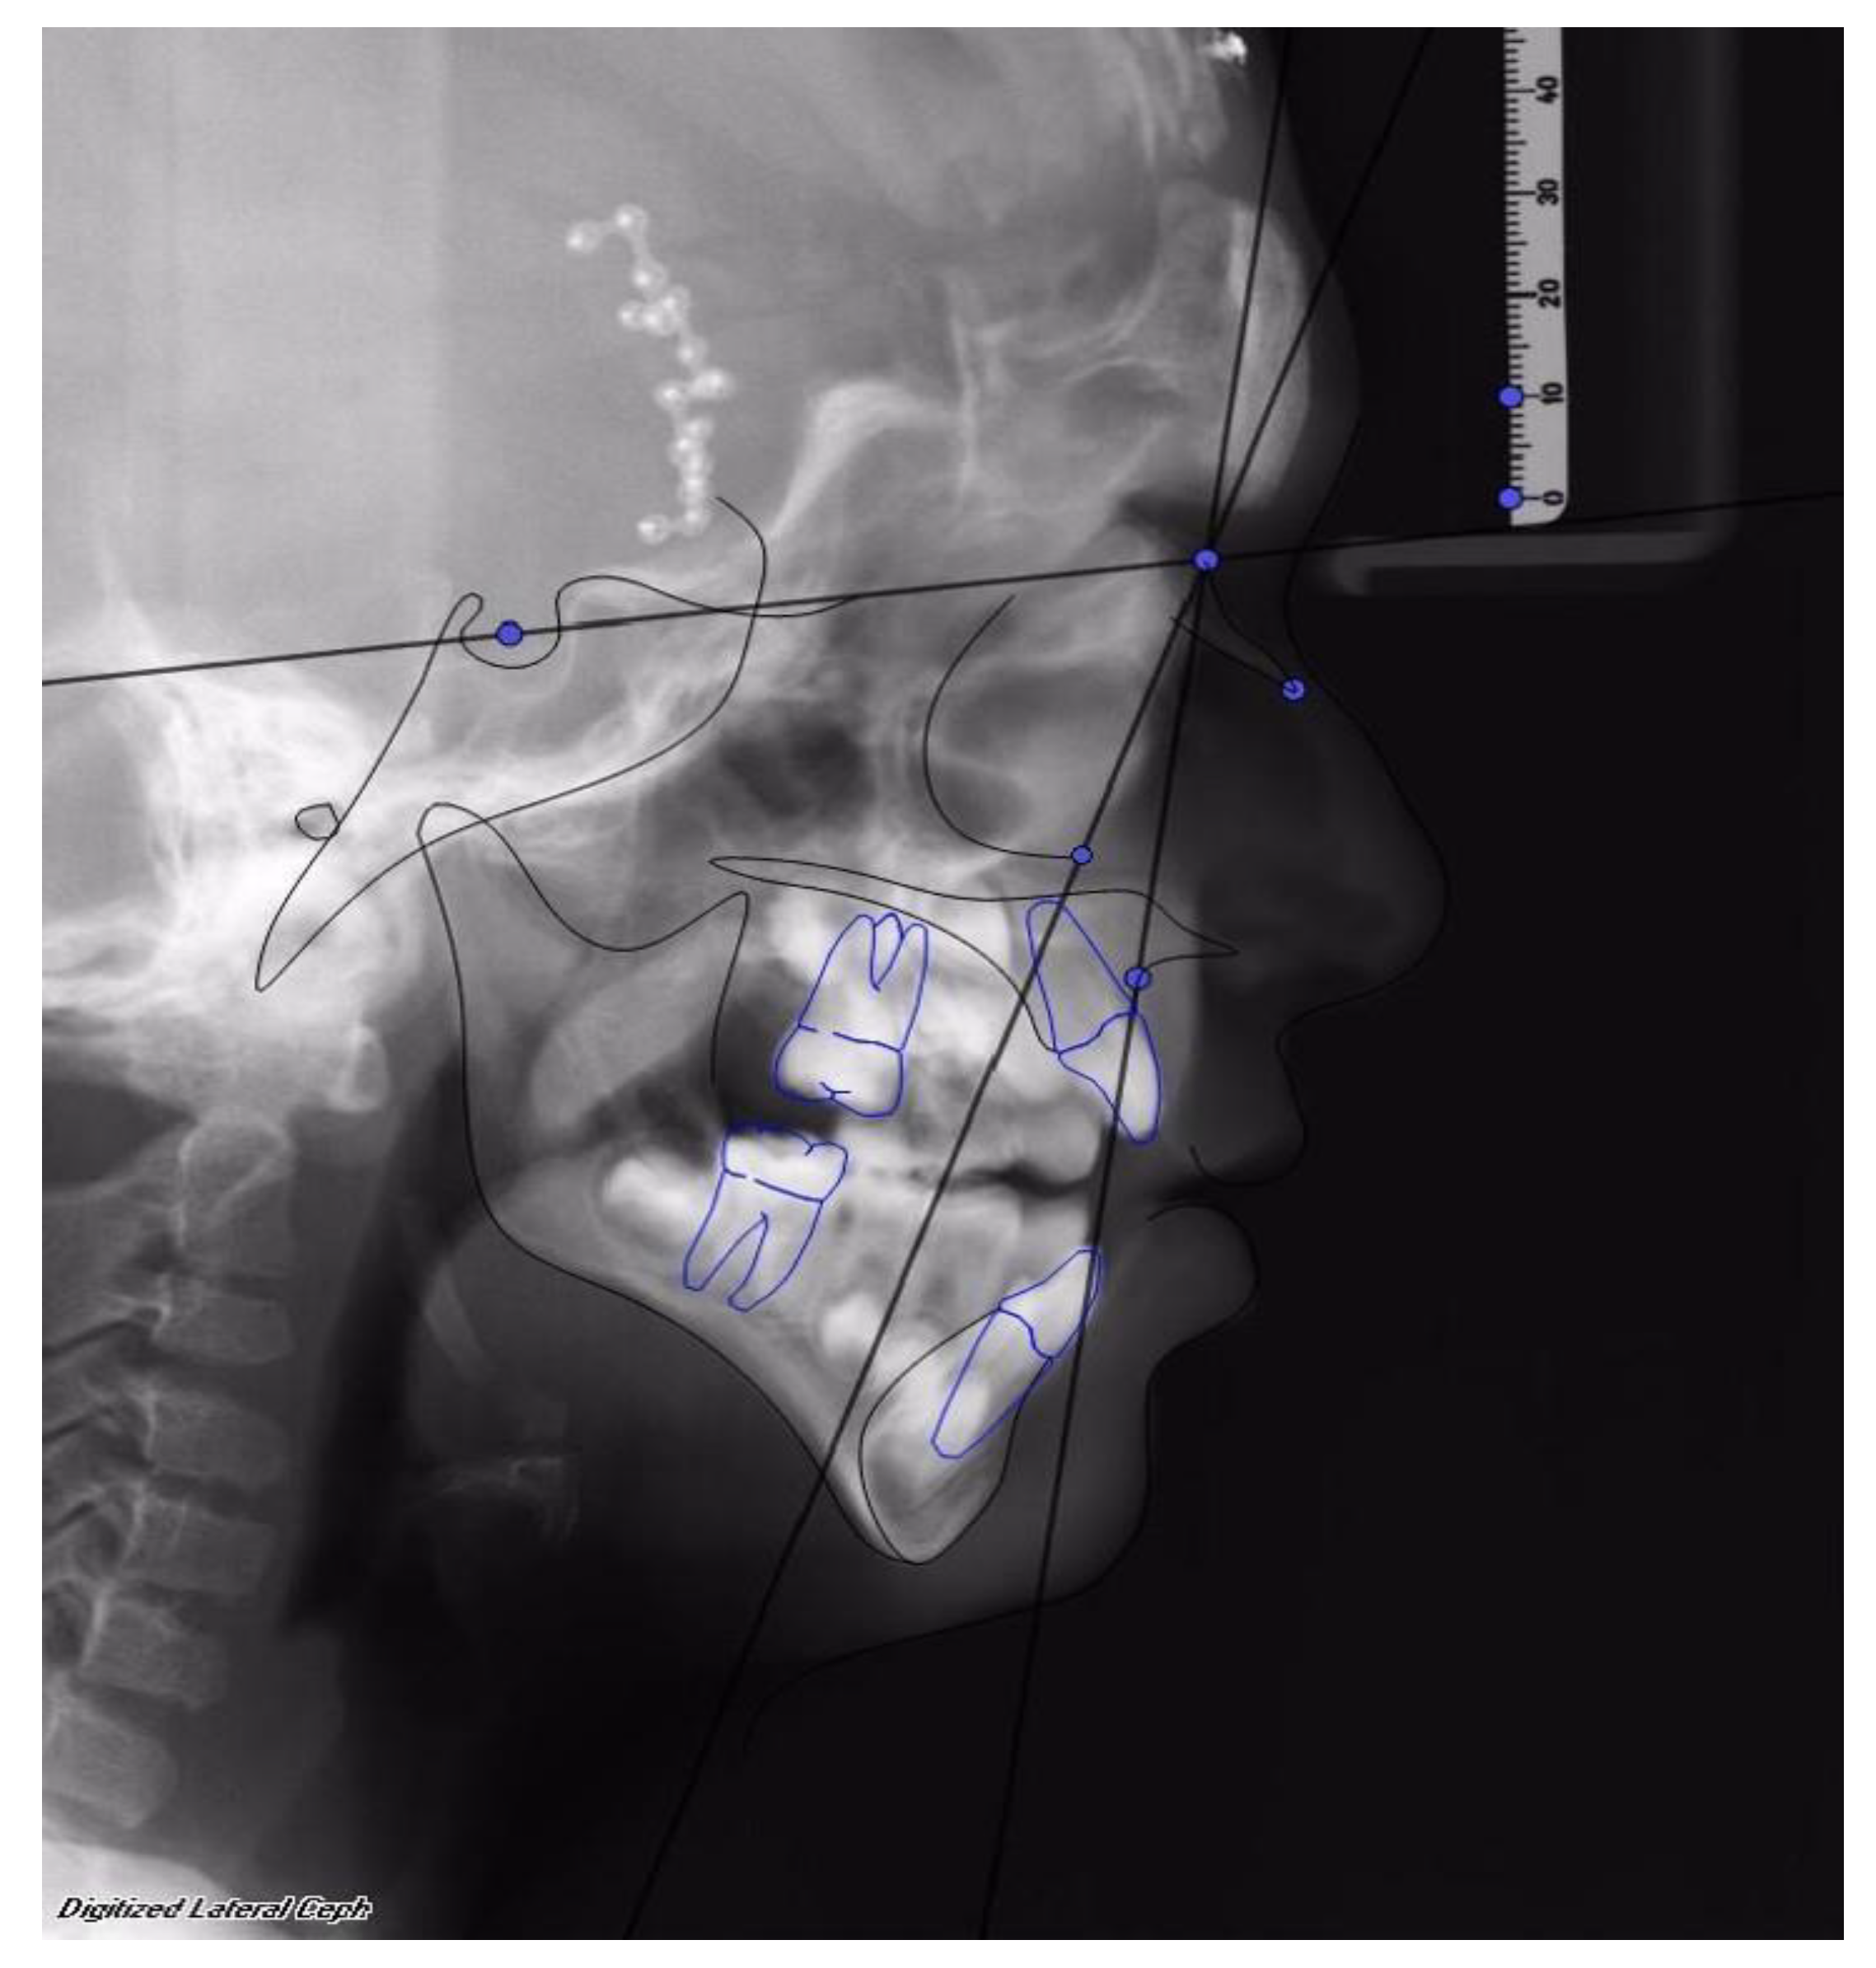

Facial advancement was satisfying for every patient, only the advancement of patient 1 should have been greater in order to reach the appropriate projection. Clinical results were anyway satisfying, so no further surgical procedure was undertaken. (See Figure 2 and Figure 3).

Figure 2. First patient, female, 6 years old, affected by Crouzon’s Syndrome. Osteodistraction (OD) was removed after 40 days before the established time of osteodistraction for fractures of bone support caused by accidental trauma. Osteodistraction was finished with an advancement of 23 mm. The advancement was interrupted before the normalization of the SNA angle to stop bone advancement. After removal of the OD device, the SNA was 75° and the SNOr was 63°.

Figure 3. The same patient after 1 year from the end of treatment with MAC. SNA was 76° and SNOr was 63°.